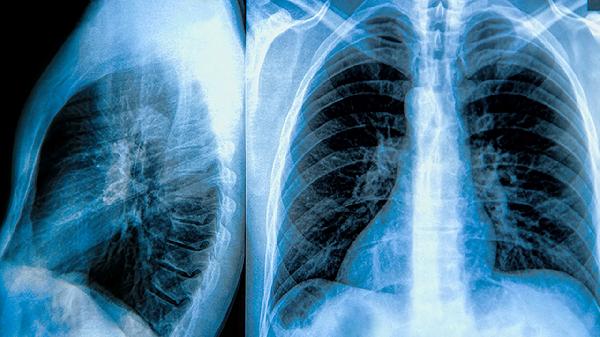

肺大泡体积增大可能压迫周围正常肺组织,导致呼吸困难加重或反复气胸发作。当肺大泡占据单侧胸腔三分之一以上空间,或合并持续胸痛、咯血等症状时,手术干预可有效改善肺功能。胸腔镜微创手术是常用治疗方式,通过切除病变组织帮助剩余肺组织复张。术前需通过胸部CT评估大泡与周围血管的解剖关系,避免术中出血风险。